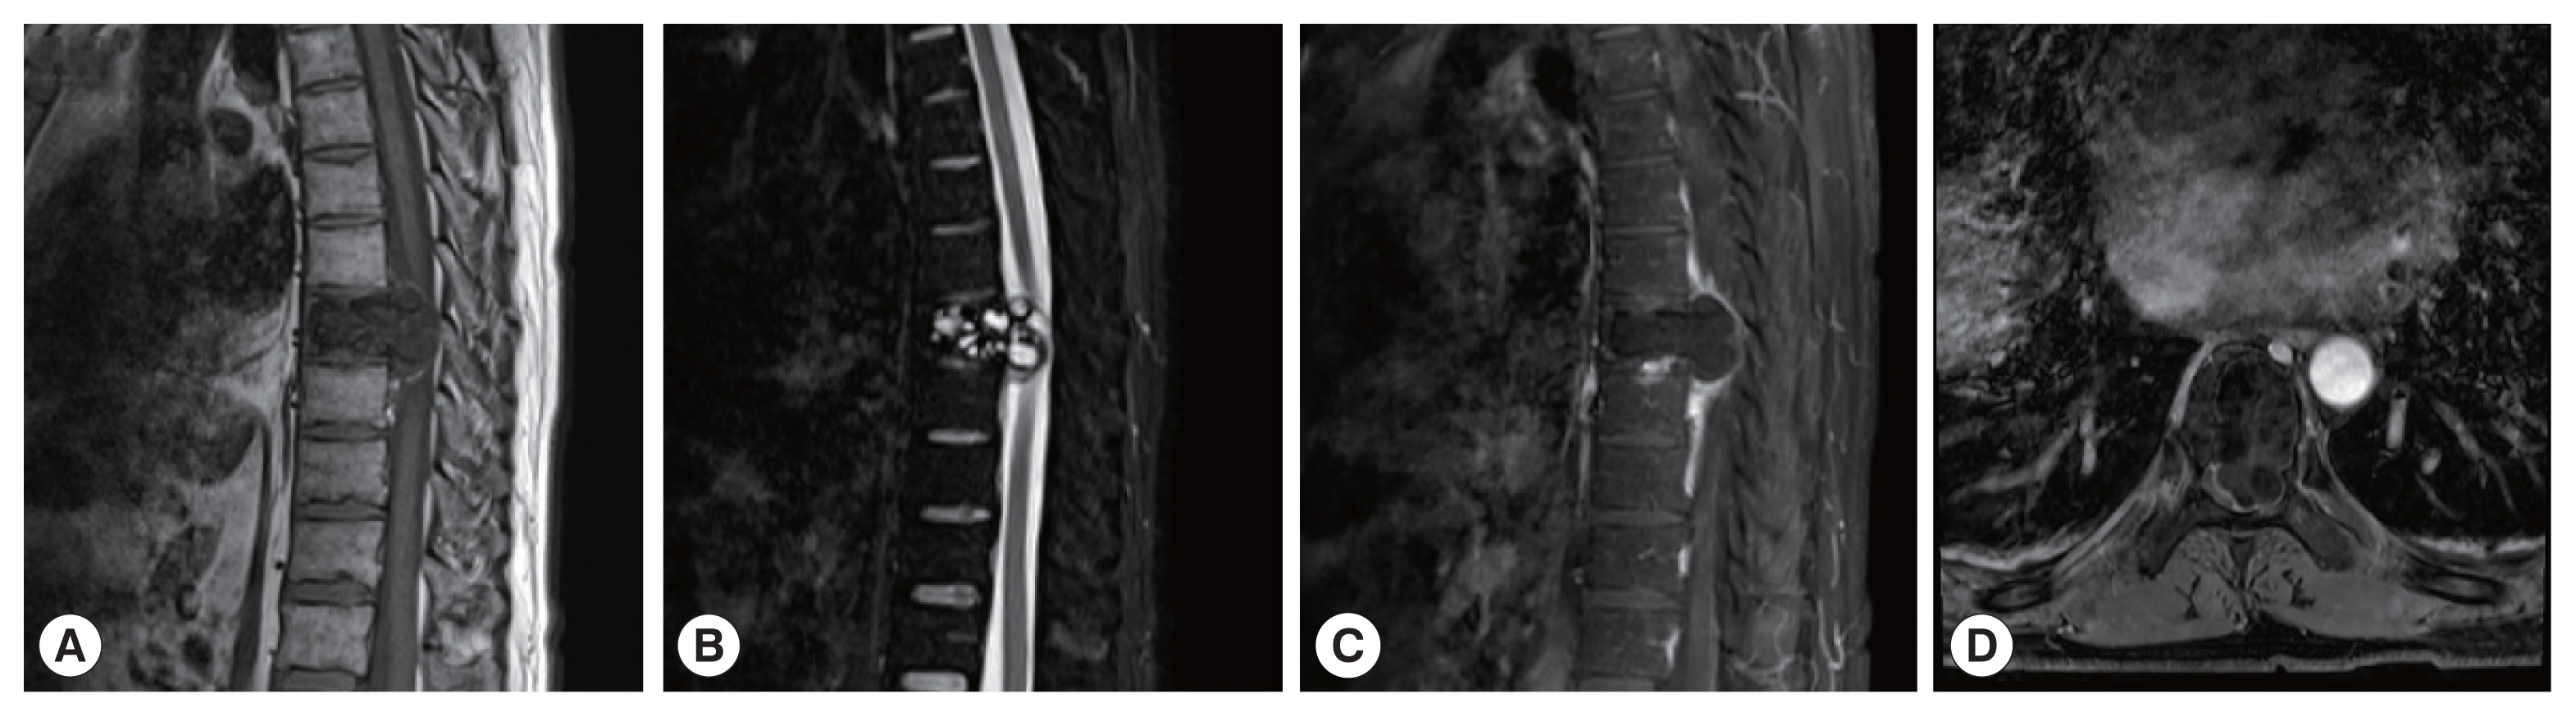

The CT images of patient 1 showed the uneven bone density and low-density bone destruction of the infected vertebral body. The boundary of the lesion was clear, but the edge was sclerotic. Multiple round low-density shadows and separation were seen, and the spinal canal was compressed and narrowed. The MRI scans also showed a low signal on T1WI, a high signal on T2WI, and a “grape bunch-like” cluster. The edge of the lesion was slightly enhanced on the enhanced scan, while no obvious enhancement was found in the interior portion. The lesion protruded into the spinal canal, causing spinal cord compression (Fig. 1). In patient 2, the lesion involving the left femoral head-femoral neck-femoral trochanter was seen on CT scan. The left femoral head, neck, and trochanter showed cystic expansive bone destruction, accompanied by sclerotic edge and dead bone formation. Local soft tissue masses were also recognized. The MRI showed an irregular low signal on T1WI, a high signal on T2WI, and a patchy high signal on T2WI in the vastus lateralis muscle (Fig. 2). Patient 3 showed osteolytic destruction of the vertebral body with wedge-shaped compression. The formation of sequestrum, intervertebral space stenosis, and swelling of the surrounding soft tissue were also noticed. In the other 3 patients (patients 4, 5, and 6), osteolytic destruction was observed, and some vertebral bodies showed wedge-shaped compression. Spinal canal stenosis and soft tissue masses were also seen locally.

One CE patient (patient 1) showed expansile bone destruction in the infected vertebral body on CT images, and polycystic changes on MR images. This patient was misdiagnosed with giant cell bone tumor. Two patients (patients 3 and 6) were misdiagnosed as tuberculosis on preoperative CT examinations because the infected vertebral body showed osteolytic bone destruction, together with sequestrum formation and soft tissue masses. Another patient (patient 4) revealed abnormal signal shadows with oval low signal on T1WI and high signal on T2WI. The patient was initially diagnosed with a neurogenic tumor due to edge enhancement on the enhanced scan.

In this study, 2 cases suffered from CE and 4 cases were from AE. The main lesions were spinal cords, which is consistent with a previous report [9]. Two CE cases were characterized by cystic expansile bone destruction, and 4 AE manifested with osteolytic bone destruction. On CT scans, both AE and CE manifest as round or oval low-density bone destruction of varying sizes, with clear lesion edges and calcification in the cyst or on the cyst wall [10,11]. MRI shows better soft tissue imaging ability than CT. For intraspinal and paravertebral hydatid disease, MRI clearly displays the number and location of hydatid cysts, which is of great value in diagnosing the disease. In this study, a low signal on T1WI, a high signal on T2WI, a high signal in the cyst contents, and a “grape bunch-like” cluster [12,13] were visible on MRI scan.